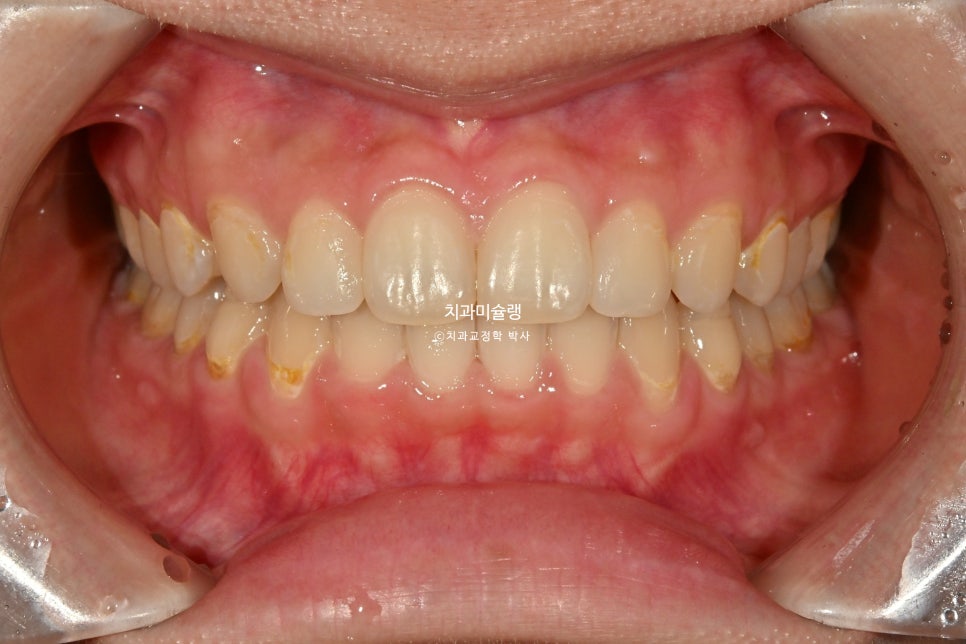

마무리 조절을 거쳐 2026년 3월, 치료를 마쳤습니다. 총 치료기간은 1년 2개월 입니다.

중심선은 정확히 맞으며 과개교합은 개선되었습니다. 브라켓 주변부 양치가 안되어 안타깝게도 충치가 좀 생겼습니다. 어금니 교합관계는 1급관계를 달성.

| 교정장치 | 인비절라인(중단) | 클리피씨 |

| 미니스크류 | 미사용 | 4개소 |

| 중심선 | 불일치 | 일치 |

| 과개교합 | 있음 | 개선됨 |

| 어금니 교합 | 2급 관계 | 1급 관계 |

| 입술부전증 | 있음 | 개선됨 |

| 턱관절 증상 | 통증 있음 | 증상 없음 |